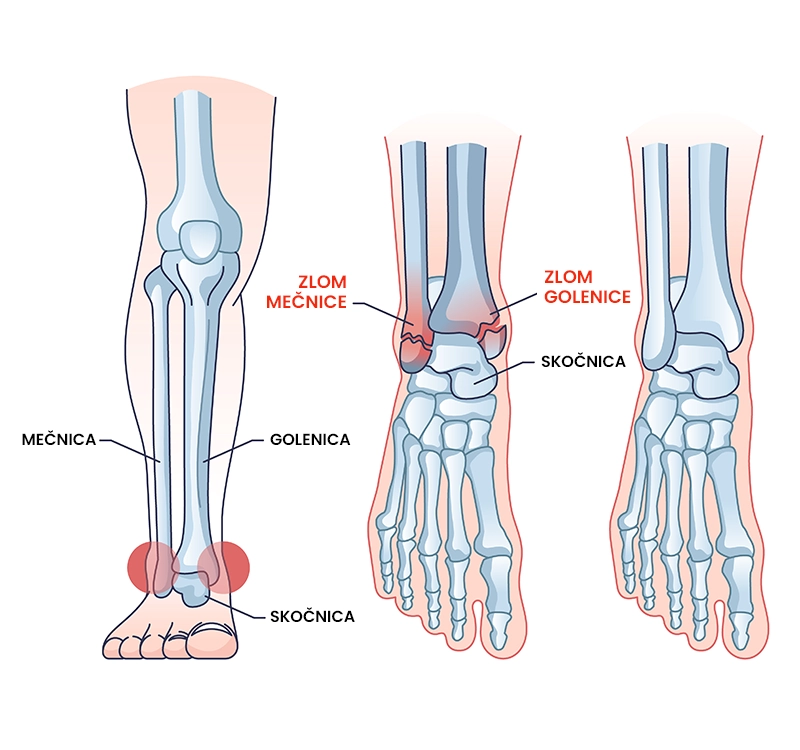

Zlom gležnja

Kaj je zlom gležnja?

Zlom gležnja je poškodbeno stanje kosti pri katerem pride do zloma spodnjega zunanjega kostnega odrastka golenice, spodnjega platoja golenice in/ali notranjega kostnega odrastka mečnice. Poškodbo glede na mesto zloma opredelimo kot unimaleolarni (zlomljen je notranji ali zunanji kostni odrastek), biomaleolarni (zlomljena sta oba kostna odrastka) in trimaleolarni  (zlom notranjega in zunanjega kostnega odrastka ter spodnjega dela platoja golenice). Zlom gležnja spremljajo takojšnja neznosna bolečina, nezmožnost obremenjevanja gležnja in spremenjena oblika sklepa. Zlom gležnja je najpogosteje posledica padcev (npr. z višine), udarcev (npr. prometna nesreča) ali prekomernih rotacij v gležnju (npr. med hojo ali tekom).